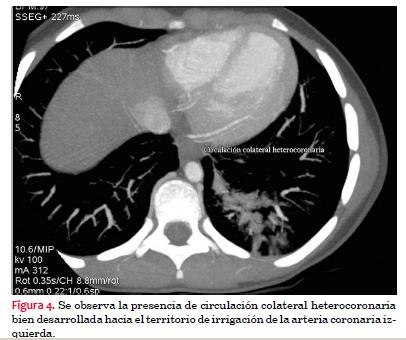

Se realiza tomografía multicorte. Adquisición en equipo General Electric de 64 receptores Lightspeed VCT con la paciente bajo anestesia general, con gating retrospectivo y con contraste intravenoso: iopromida 370 mg I/ml, utilizando un total de 20 ml bajo anestesia general inhalatoria y sin betabloqueo. Frecuencia cardíaca: 180 lpm. La buena calidad de la imagen obtenida se debe a dos aspectos: se utilizó un protocolo para frecuencias cardíacas elevadas para uso pediátrico y el pequeño tamaño corporal. No se hizo volume rendering porque a esa frecuencia cardíaca la imagen es de pésima calidad para esa técnica, no así para la imagen angiográfica. Se hace diagnóstico anatómico de origen anómalo de arteria coronaria izquierda en arteria pulmonar (figuras 2, 3, 4 y 5).

El ecocardiograma bidimensional y con Doppler color muestra la dilatación e hipocontractilidad ventricular izquierda así como insuficiencia mitral. Se asocian signos indirectos de esta patología como la presencia de una arteria coronaria derecha dilatada y ausencia de visualización del origen de la arteria coronaria izquierda desde la aorta, y signos directos como un flujo de entrada en la arteria pulmonar y la presencia de un flujo centrípeto (desde la periferia al centro) por la arteria coronaria izquierda (figura 9). En determinadas situaciones puede ser difícil la interpretación del ecocardiograma, como en casos de hipertensión arterial pulmonar, existente en los neonatos o en niños con severa falla del ventrículo izquierdo, lo que genera un flujo anterógrado en la coronaria anómala, con escasa dilatación de la coronaria derecha.